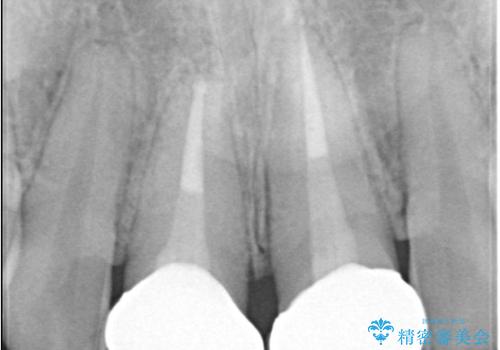

- 以前他院で治療した前歯の被せものの見た目の不満を主訴にご来院されました。レントゲンと診査の結果、被せものの不適合だけでなく、その土台となる歯の根管充填(根の治療の詰め物)が不十分であることが判明。再感染のリスクを避けるため、まず精密根管治療を行い、その後に最も審美性に優れたオールセラミッククラウンで修復する治療計画を立案しました。これにより、見た目の改善と歯の寿命の長期化を目指しました。

治療は、再感染の原因となっていた粗な根管充填材を丁寧に取り除く精密根管治療から開始しました。治療中はラバーダムと歯科用顕微鏡を使用し、根管内を徹底的に清掃・消毒。根の先まで緊密に薬を詰めることで、再発リスクを最小限に抑えました。根管治療の完了後、歯ぐきの状態を整え、周囲の歯と調和するオールセラミッククラウンを作製。金属を一切使わないため、透明感のある自然な仕上がりとなり、長年の見た目のコンプレックスも解消。歯の内部から表面までを根本的に改善することができました。